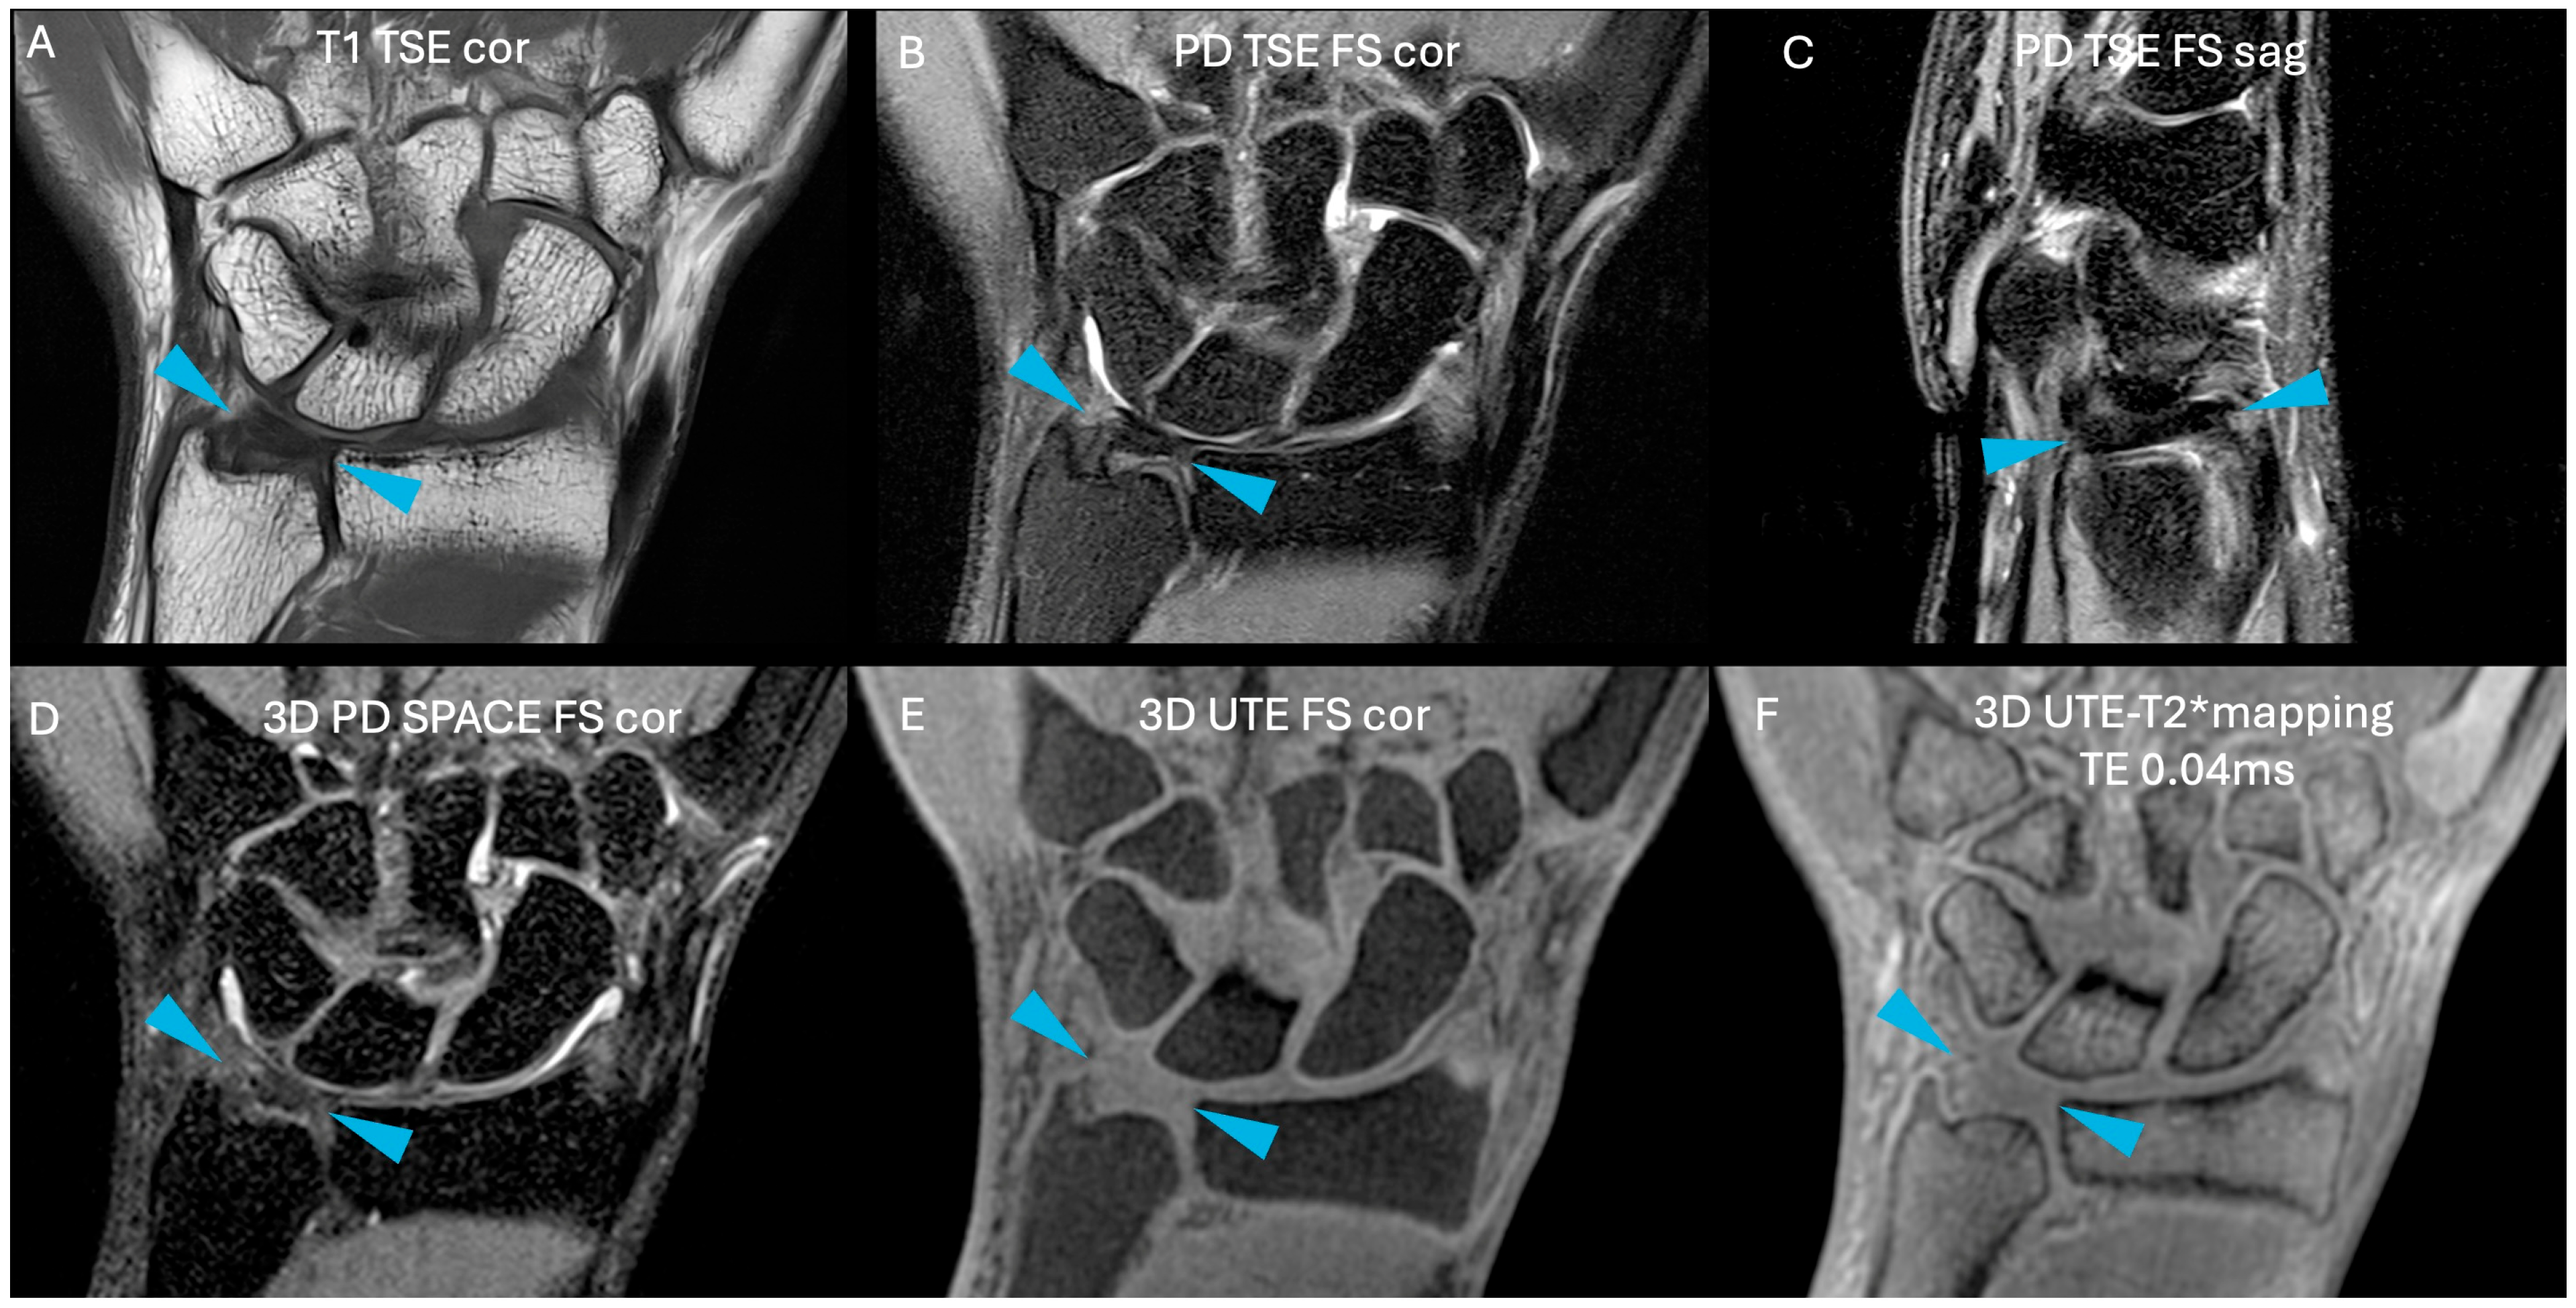

Images were free of artefact, allowing optimal visualization of the TFCC in all cases. No cases of central TFC perforation or additional TFCC injuries were detected. An example of the sequences acquired for one volunteer is shown in Figure 1. Figure 2 presents the multiple echoes of the 3D UTE-T2* mapping sequence along with the resulting UTE-T2* map. TFC segmentation on a single slice of the UTE-T2* map is illustrated in Figure 3 for three volunteers with different ages.

Figure 2. (AD): the same slice of the four different TEs used in the 3D UTE-T2* mapping sequence; (E) the resulting UTE-T2* map in grayscale, and (F) the UTE-T2* map in color (using the “RAINBOW” colormap in Osirix). The scaling is set from 0 to 300 a.u., corresponding to 0 to 30 ms. Increasing TE will cause tissues with short T2 relaxation times (e.g., fat) to appear hypointense, while tissues with long T2 relaxation times (e.g., muscle) will appear hyperintense. Blue arrows indicate TFC.